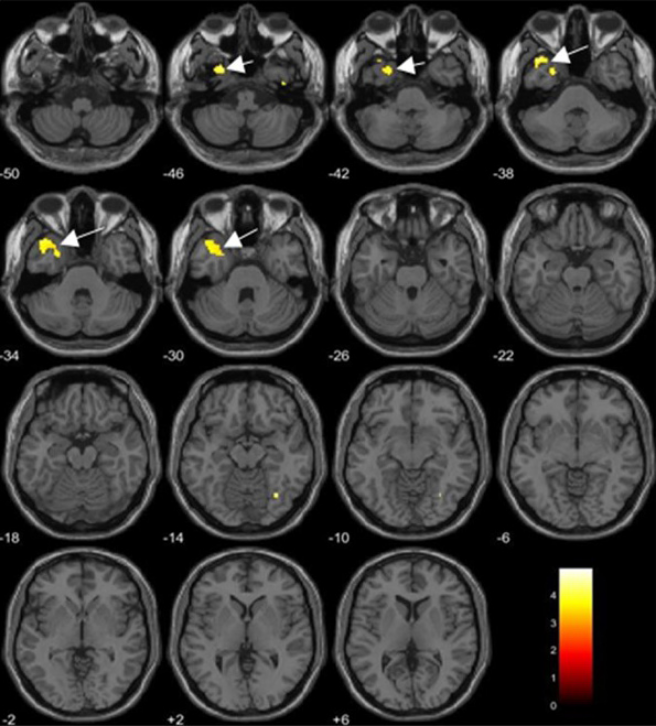

ダイオキシンの血中濃度と脳体積の相関について評価しています。

有意な負の相関を示す脳領域(p < 0.05でFDR補正)を黄色と矢印で示しています。

左:ダイオキシン類の1つであるTCDDの血中濃度と脳体積の相関を評価

右:ダイオキシン類の1つであるPCDDの毒性を1としたときの毒性当量(TEQ-PCDD)の血中濃度と脳体積の相関を評価

Alterations in Regional Alterations in Regional Brain Regional Volume Associated with Dioxin Exposure in Men Living in the Most Dioxin-Contaminated Area in Vietnam: Magnetic Resonance Imaging (MRI) Analysis Using Voxel-Based Morphometry (VBM) より引用​